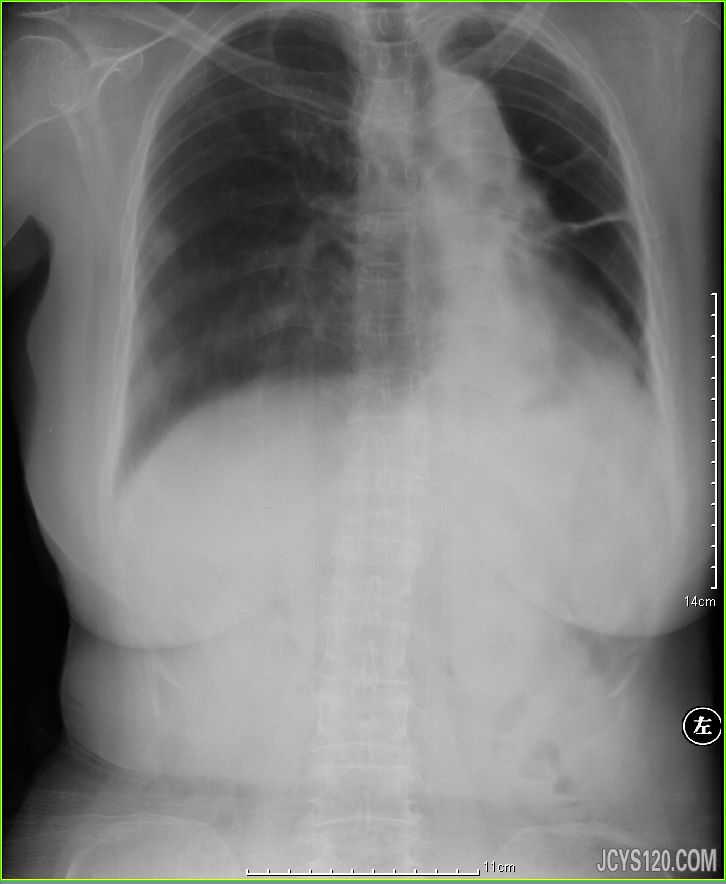

男,60岁,躯体活动受限。 我仅仅是上传了部分能够看清楚的X光片,大家先讨论 **** 本内容被作者隐藏 **** 阅读全文>

患者女,50岁,结合病史数年,进来呼吸困难进行胸部X线检查。 阅读全文>